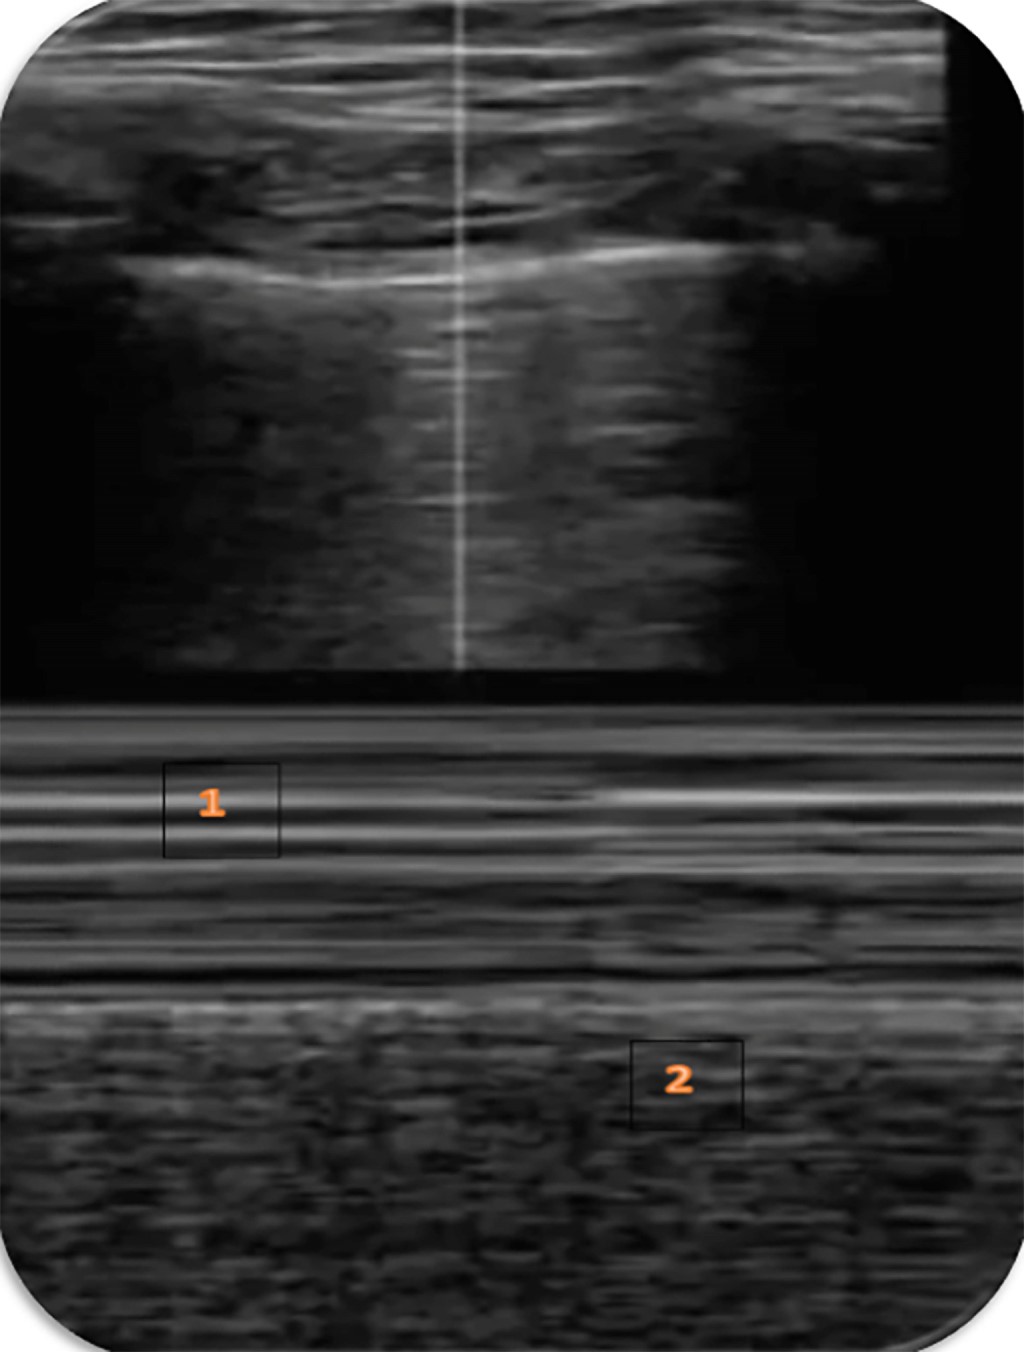

En modo M podemos ver la imagen en "arena de playa" constituida por un patrón lineal que corresponde a la pared torácica inmóvil, una línea hiperecogénica (la línea pleural) y un patrón granulado que correspondería al tejido pulmonar en movimiento. Este patrón granulado es más claro durante la inspiración permitiendo distinguir la fase respiratoria (Figura 2)(5).